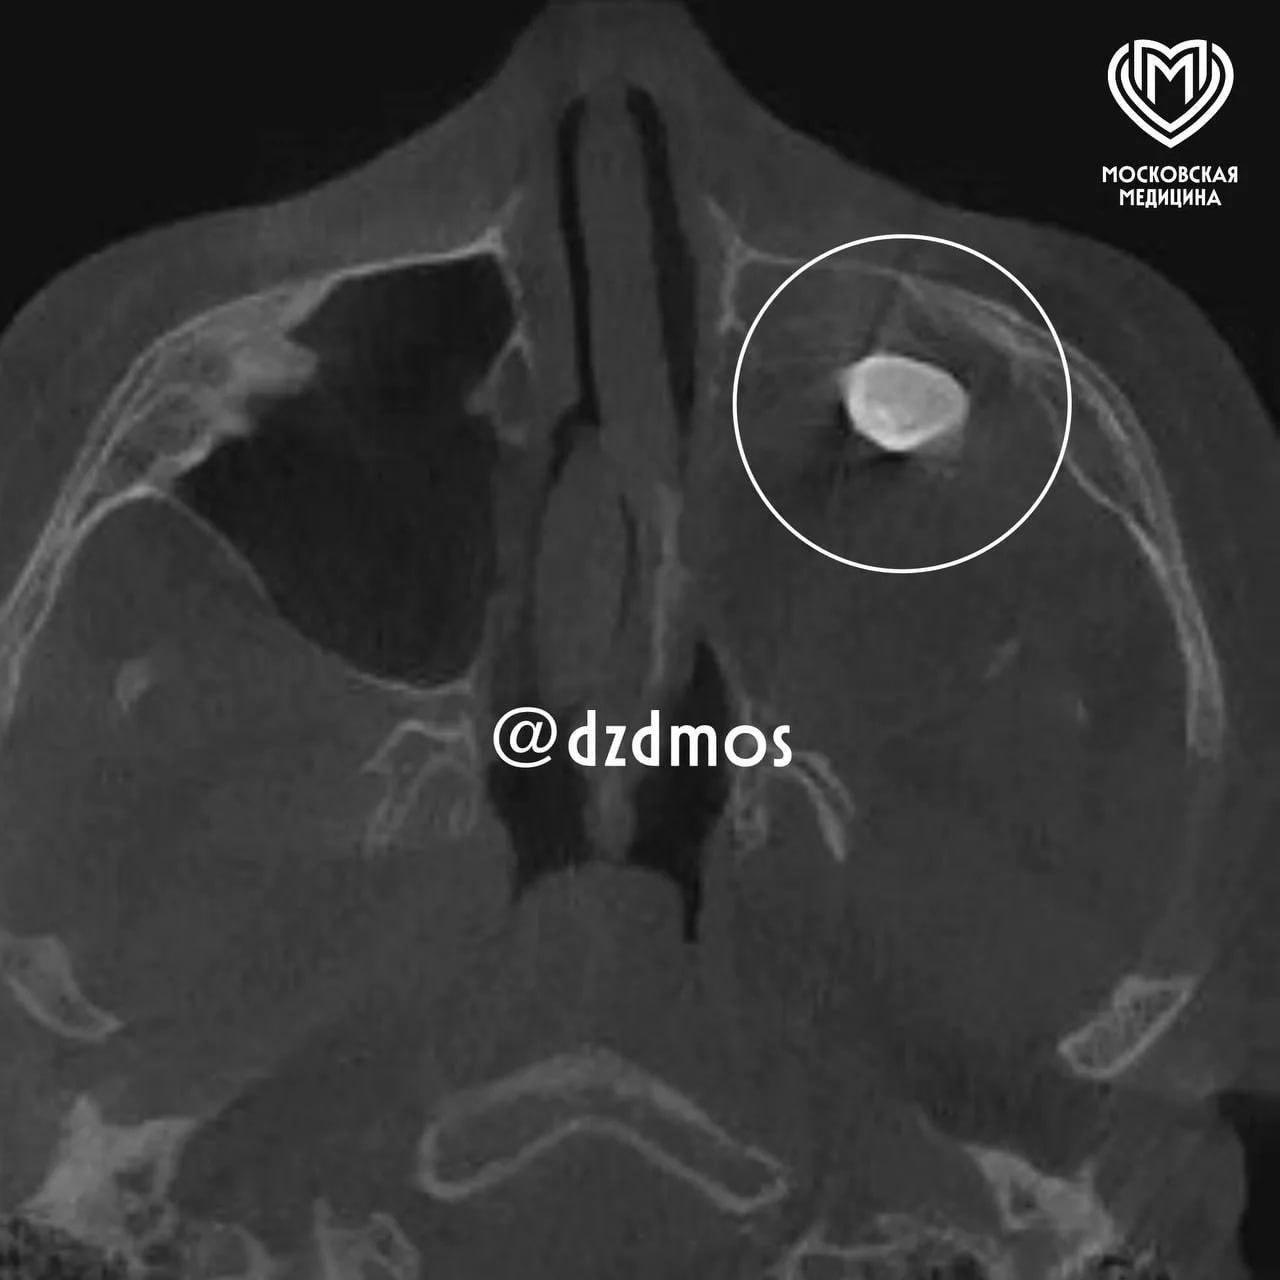

Московские врачи провели необычную операцию: они удалили зуб, который обнаружился… в носу у подростка. Звучит как сценарий из фильма ужасов, но это реальный случай, который наглядно демонстрирует, как сложно и иногда непредсказуемо устроен человеческий организм.

Оказалось, что этот зуб был частью тератомы — редкого вида новообразования, которое может содержать ткани, несвойственные для конкретного участка тела. Внутри тератомы могут находиться волосы, ногти, мышечные волокна, кости и даже зубы. Это происходит из-за сбоя в процессе эмбрионального развития, когда клетки начинают формировать структуры, которые им не предназначены.